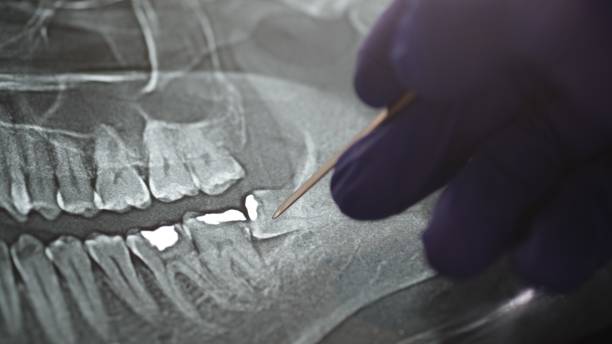

تأخذ اللثة عند التهابها لوناً أحمر وتصبح متورمة وتنزف بسهولة. غالبًا ما يجري اعتماد التشخيص بناءً على فحص طبيب الأسنان للثة المريض. تساعد الصحة الفموية الجيدة، وتنظيف الأسنان بشكل يومي، بالإضافة إلى التغذية الكافية، على القضاء على التهاب اللثة والوقاية منه .